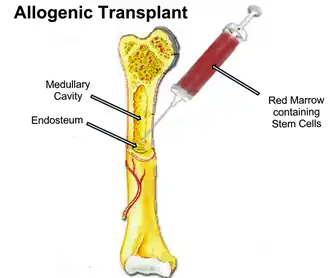

Stem Cell Transplants are a common method of treatment which can either be used in conjunction with chemotherapy to improve remission and effectiveness or it can be used with relapsed lymphoma patients.[6] Stem cell transplants can either be an autologous stem cell transplant (ASCT) in which the patient donates their own stem cells or an allogeneic stem cell transplant (alloHCT) in which a related or unrelated healthy donor will donate their stem cells to the patient.[3] Stem cells are collected from the bone marrow and are a type of cell capable of self-renewal and can differentiate into all types of cells,[2] this can be utilised for patients with T-cell lymphoma and has seen effective results in treating some subtypes, especially Angioimmunoblastic T-cell lymphoma.[8]

Allogenic stem cell transplants are mainly used when the patient lacks adequate healthy stem cells for an autologous stem cell transplant or has relapsed after prior autologous stem cell transplant treatments.[8] However, allogenic transplants pose a risk as it may be toxic to the patient. Proposed solution include improved donor selection and the use of a conditioning regime in which a high dose of a myeloablative treatment is given alongside stem cell transplants to reduce the immune response.[2]